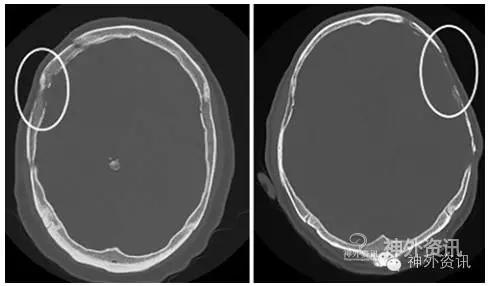

自体骨瓣从术中取下来后,置于-80°C的深低温无菌敷料中保存;破碎骨片先用钛连接片拼接成形。人工材料包括陶瓷、聚醚酮树脂和钛合金板等,根据CT三维成像技术塑造出理想的形状。颅骨修补术后6周、3个月、6个月、12个月和以后每年定期CT随访。根据骨质吸收的影像学表现分为两种类型,I型:骨质变薄;II型:颅骨内板和外板完全吸收。II型患者需进行再次修补手术(图1)。

图1. 两种骨质吸收类型。左图为I型,骨质变薄;右图为II型,局部骨质完全吸收